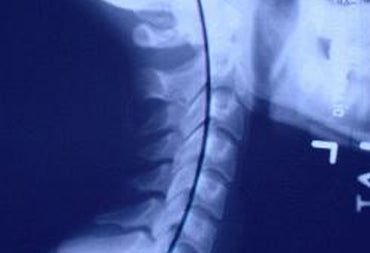

Let me start off by describing what correct neck alignment is. Ideal alignment is having your neck straight up and down when looking at your posture from the front or back. When looking from the side you should have a smoothing flowing C-curvature. This squidoo lens will showcase for you what a normal and abnormal neck curve look like on x-ray.See the Person's X-ray on the Left ?- that looks like a pretty good neck curve, good neck alignment. Notice the backwards "C" line that is drawn on the x-ray? It has something to do with that. Keep reading for more information about neck alignment and having it the best you can get.

By having a neck x-ray. Specifically a lateral cervical neck x-ray. This is an x-ray from the side of your neck. Also, another good x-ray to look at is called the AP cervical x-ray: from the anterior and posterior (from the front and from the back). These two views will give you a good indication of your neck alignment. You have to know what your neck alignment is before you can start correcting it.On the lateral neck picture above one can draw a line along the backs of all of the vertical bodies. This is what should look like a "C".

Here is a normal neck curve. This person is standing on their side, looking to the right. Notice the #1-7 labeled on the x-ray. Those represent the 7 bones in the cervical spine: C1, C2, C3, C4, C5, C6, C7.In terms of alignment,Notice next that the there is a backwards "C" that we could draw on the x-ray to show off the curve. If you cannot visualize the "C" look at the top of this lens.